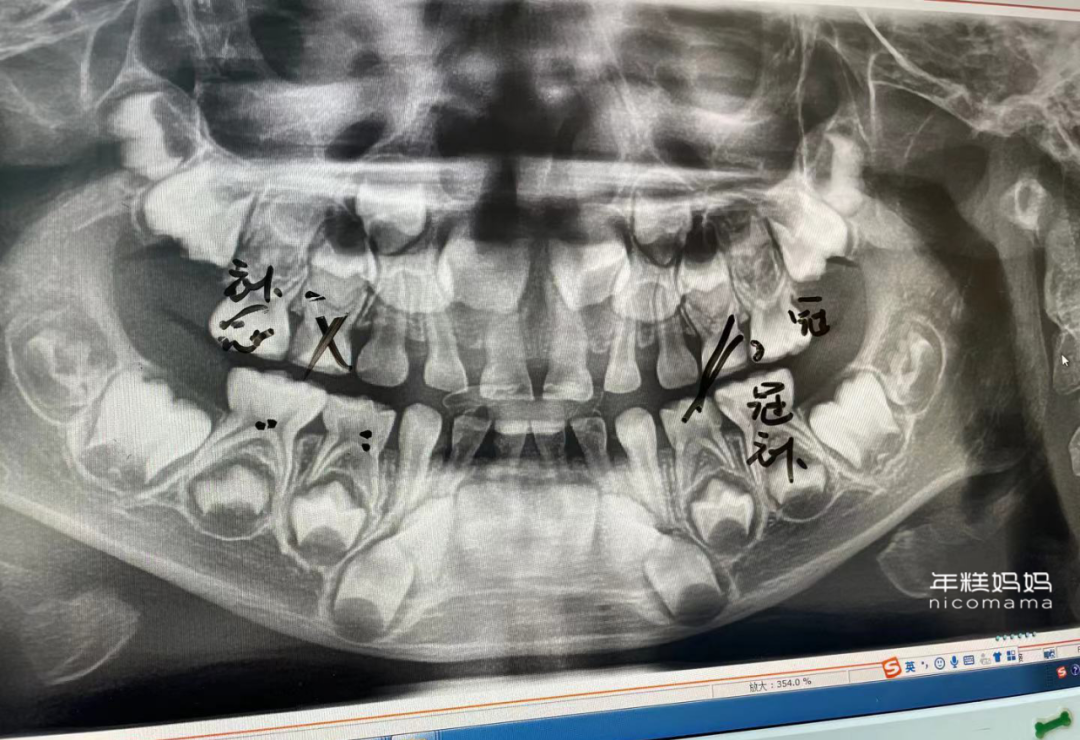

▲娃年纪小小,牙齿问题倒是一堆